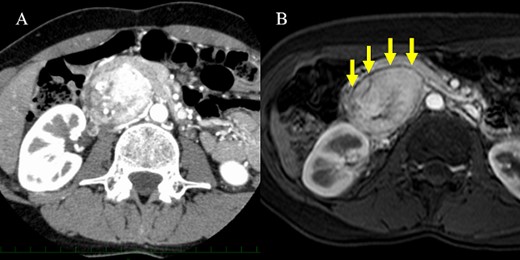

A 36-year-old woman was referred to our hospital due to a complaint of abdominal distension with concomitant symptom of excessive sweating. Abdominal contrast-enhanced computed tomography (CT) scan showed a 7.3 × 5.3 cm2 hypervascular tumor located posterior to the pancreatic head in the arterial phase (Fig. 1A). There was no evidence of a continuous beak sign from the pancreatic parenchyma to the tumor wall. A fine discontinuity of the pancreas was more clearly observed on fat-saturated T1-weighted magnetic resonance imaging (MRI) than on CT scan (Fig. 1B). The patient’s urinary norepinephrine level was elevated; hence, she was diagnosed with PGL preoperatively. Alpha-adrenergic blockers were administered preoperatively to prevent blood pressure fluctuations. Then, the patient underwent tumor resection, and she had an uneventful course without postoperative complications.

CT scan and MRI. (A) The hypervascular tumor was located dorsal to the pancreatic head in the arterial phase of contrast-enhanced CT scan. However, the outline of the tumor adjacent to the pancreas was somewhat unclear. (B) Fat-saturated T1-weighted MRI showing a clear plane between the tumor and pancreas.

The differential diagnoses of a hypervascular tumor in and around the pancreas include pancreatic neuroendocrine tumor (pNET), GIST and solid pseudopapillary neoplasm. Peripancreatic PGL and pNET are more likely to have similar radiologic findings. Thus, they are often challenging to distinguish. In a previous report, the identification of a fat plane between the mass and the adjacent pancreas may indicate PGL [5]. The beak sign and the feeding arteries are also useful in assessing the origin of the tumor organ [6]. Therefore, imaging findings that are indicative of an extra-pancreatic lesion such as the presence of a fat plane or the absence of a beak sign are important in considering peripancreatic PGL as a differential diagnosis. As shown in Case 1, fat-saturated MRI may be more effective in detecting a fat plane than CT scan in some patients. If imaging findings indicate that the tumor is extrapancreatic, a comprehensive work-up can be useful in obtaining an accurate preoperative diagnosis of peripancreatic PGL. The urinary or plasma levels of catecholamines and their metabolites are used to diagnose PGL [7]. In a previous report, 66.6% of patients with PGL had elevated urinary norepinephrine levels [8]. A previous report showed that the combined sensitivity based on three catecholamine studies was 89.9%, and the false-negative rate was 14.2% [9]. Among our patients, five underwent the 24-hour urine test, and all of them had elevated urinary normetanephrine or norepinephrine levels. Therefore, catecholamine levels should be measured if PGL is suspected on imaging studies. In addition, MIBG scintigraphy can be performed to validate the preoperative diagnosis based on the laboratory tests and to search for multicentric lesions [9].